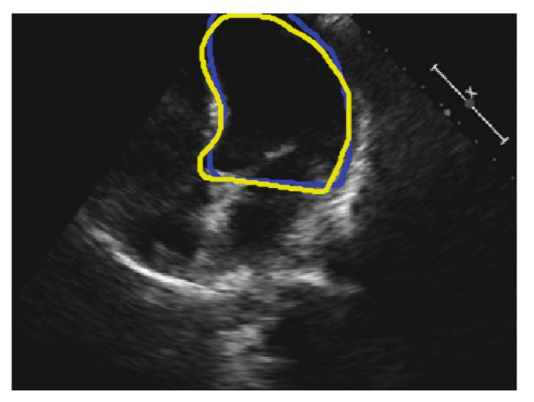

Fig. 1. An example 2D 4-chamber view. The blue and yellow curves represent the annotations by Operator-A and Operator-B, respectively.

The study population consisted of 61 patients (30 males), with a mean age of 64 ± 11, who were recruited from patients who had undergone echocardiography with Imperial College Healthcare NHS Trust.

Each patient underwent standard Transthoracic echocardiography using a Philips iE33 system by experienced echocardiographers. Apical 4-chamber views were obtained following standard clinical guidelines.

A total of 992 frames were manually annotated by two operators, with annotations used as the ground truth for model training and comparison.